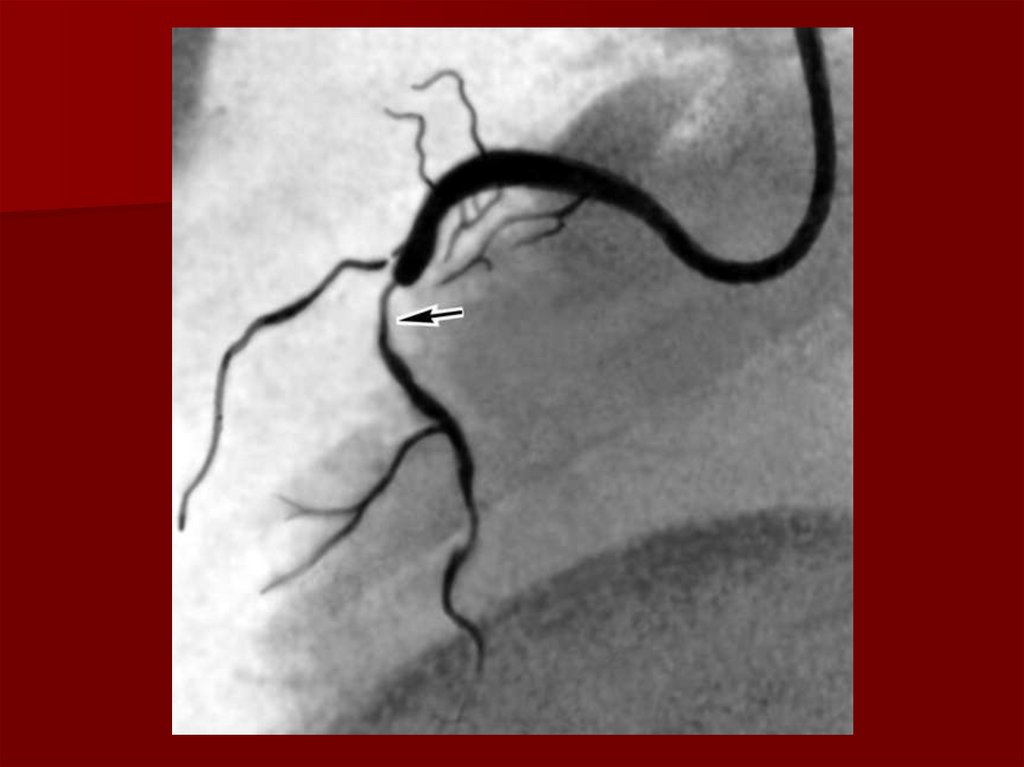

20. Инстументальные методы диагностики

Коронарография

Коронарография (решает только врач исходя из

состояния здоровья пациента).